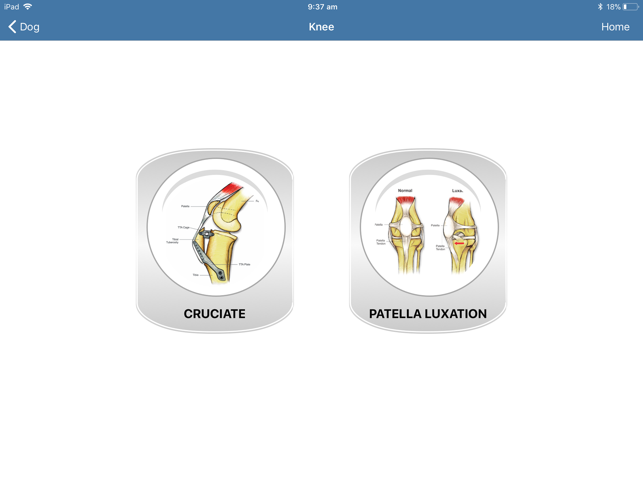

Increase value to your services

Are you still trying to explain a surgical procedure to your client using hand gestures or by stick drawings? Really? You want a client to say 'Yes' to a $3,000 TTA procedure with charades? With so much competition in the veterinary industry, you can't afford for a client to go for a second opinion or Dr Google themselves out of the procedure altogether. The iConsult will effectively and professionally help you educate your clients. There will be no need for Dr Google or second opinions.